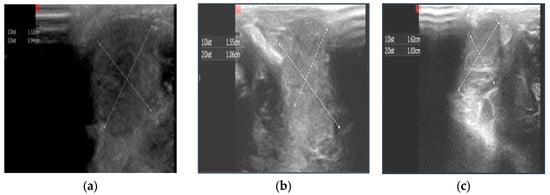

Ultrasound Measurements of Testicular Size After Exposure to Cisplatin Chemotherapy in Adult Male Rats †

3. Results and Discussion